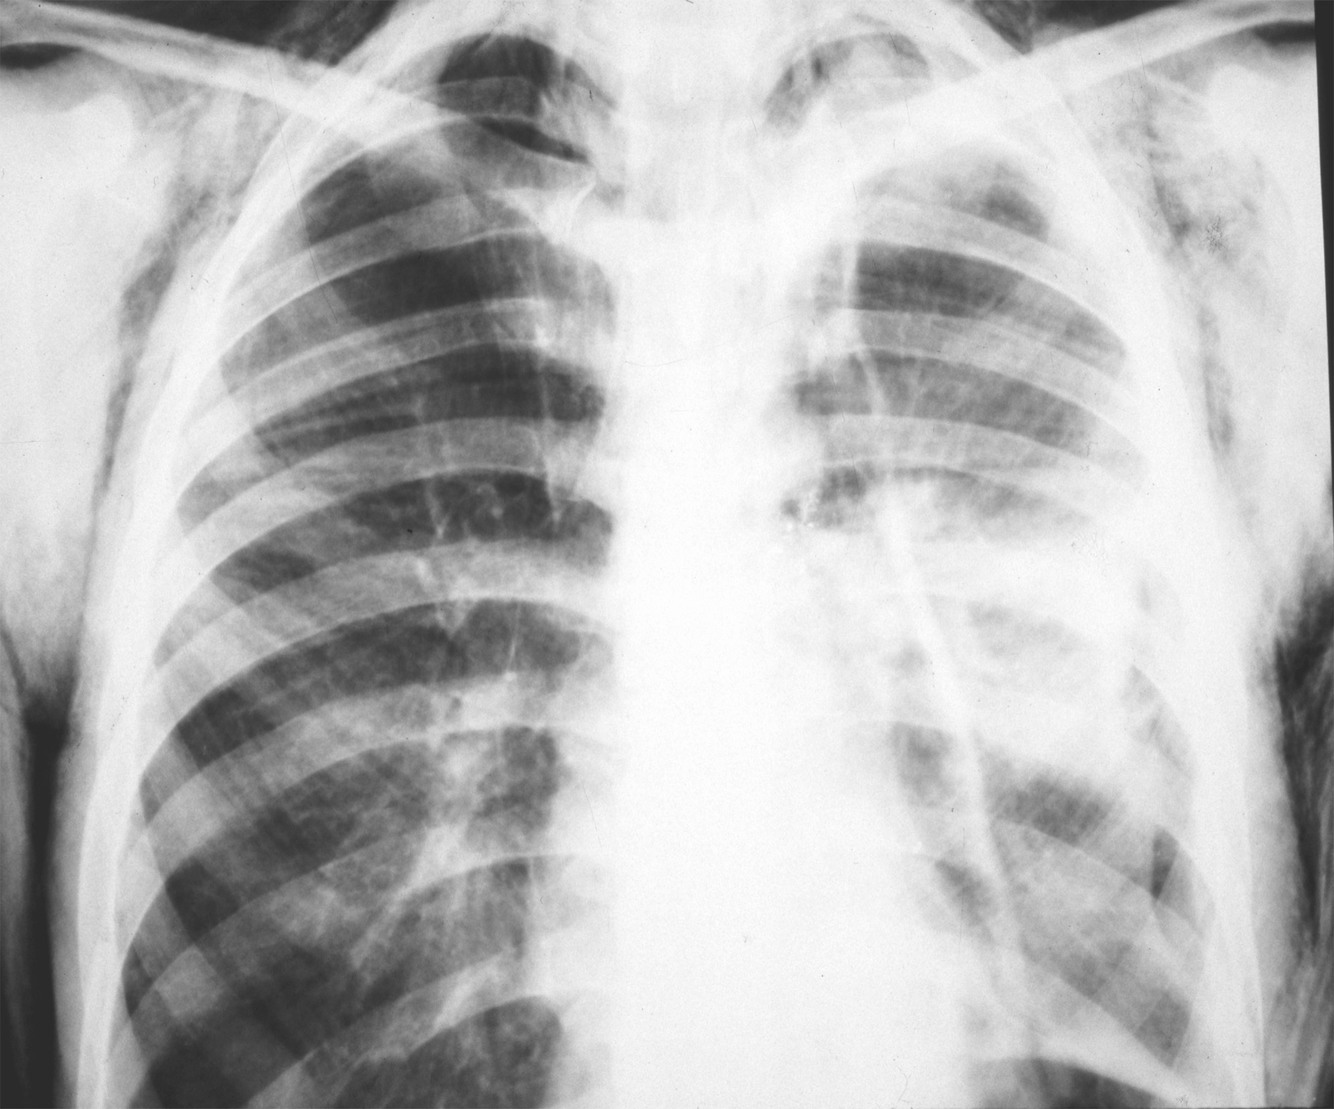

Paciente vítima de trauma torácico com fraturas em >2 arcos costais consecutivos em pelo menos 2 pontos em cada arco, com dor e respiração paradoxal…

Diagnóstico, conduta e complicação…

TÓRAX INSTÁVEL

Respiração paradoxal

retração do tórax durante inspiração e abaulamento do tórax durante expiração

Conduta: suporte: analgesia e O2

Complicação: contusão pulmonar (consolidação)

Se PaO2 < 60 ou SatO2 <90%: IOT + VM